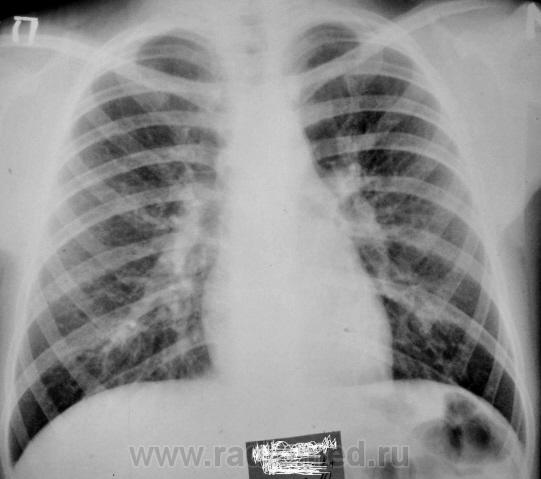

Девочка 10 лет. В течении трех недель беспокоит кашель, насморк, температуры не было, контакт с ОРВИ по дому. На 7.09.10 в легких выслушиваются разнокалиберные хрипы по всем полям,кашель, насморк. За весь период болезни получила симптоматическую терапию (климбутерол, виброцил, зиртек, эреспал, грудной сбор, физиотерапия). В ОАМ и ОАК без изменений.

Мне тоже кажется, что корни расширены. Бронхоаденит тут не исключить. Требует дальнейшего обследования, оптимально - КТ груди с внутривенным контрастированием, для лучшей визуализации структур средостения. При отсутствии возможности - линейные томограммы.

Картину можно объяснить ОРВИ - тогда:

- при сохраняющейся избыточности, неоднородности легочного рисунка, расширении корней - ПОСМОТРЕЛ бы (паренхиму заодно) - КТ ОГК!